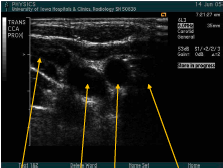

what are the arrows pointed to? what approach is being used?

trans CCA prox